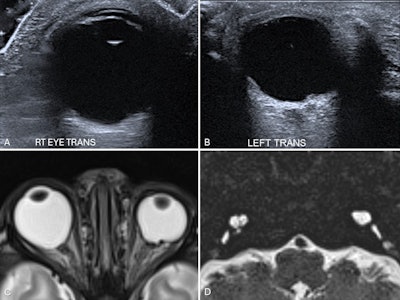

Bilateral congenital cataracts in a 15-day-old infant. Axial ultrasound images of the right lens (A) and left lens (B) demonstrate increased thickness with intralenticular echoes and increased echogenicity of both the anterior and posterior lens walls. (C) Left cataract in a different 2-year-old child with left retinoblastoma. Axial T2-weighted fat-saturated (T2W FS) MRI of the orbits shows globular thickening of the left lens with increased T2 signal compared to the normal right lens, consistent with cataract formation. Additional findings include left retinal detachment and mucosal thickening of the bilateral ethmoid air cells. Attachment of the retinal membrane to the optic disc is not visible in this image. All figures courtesy of Drs. Lasith Ihalagamage, Albert Prat Matifoll, Robert Goetti, and Kristina Prelog and presented at RANZCR's 2025 ASM.